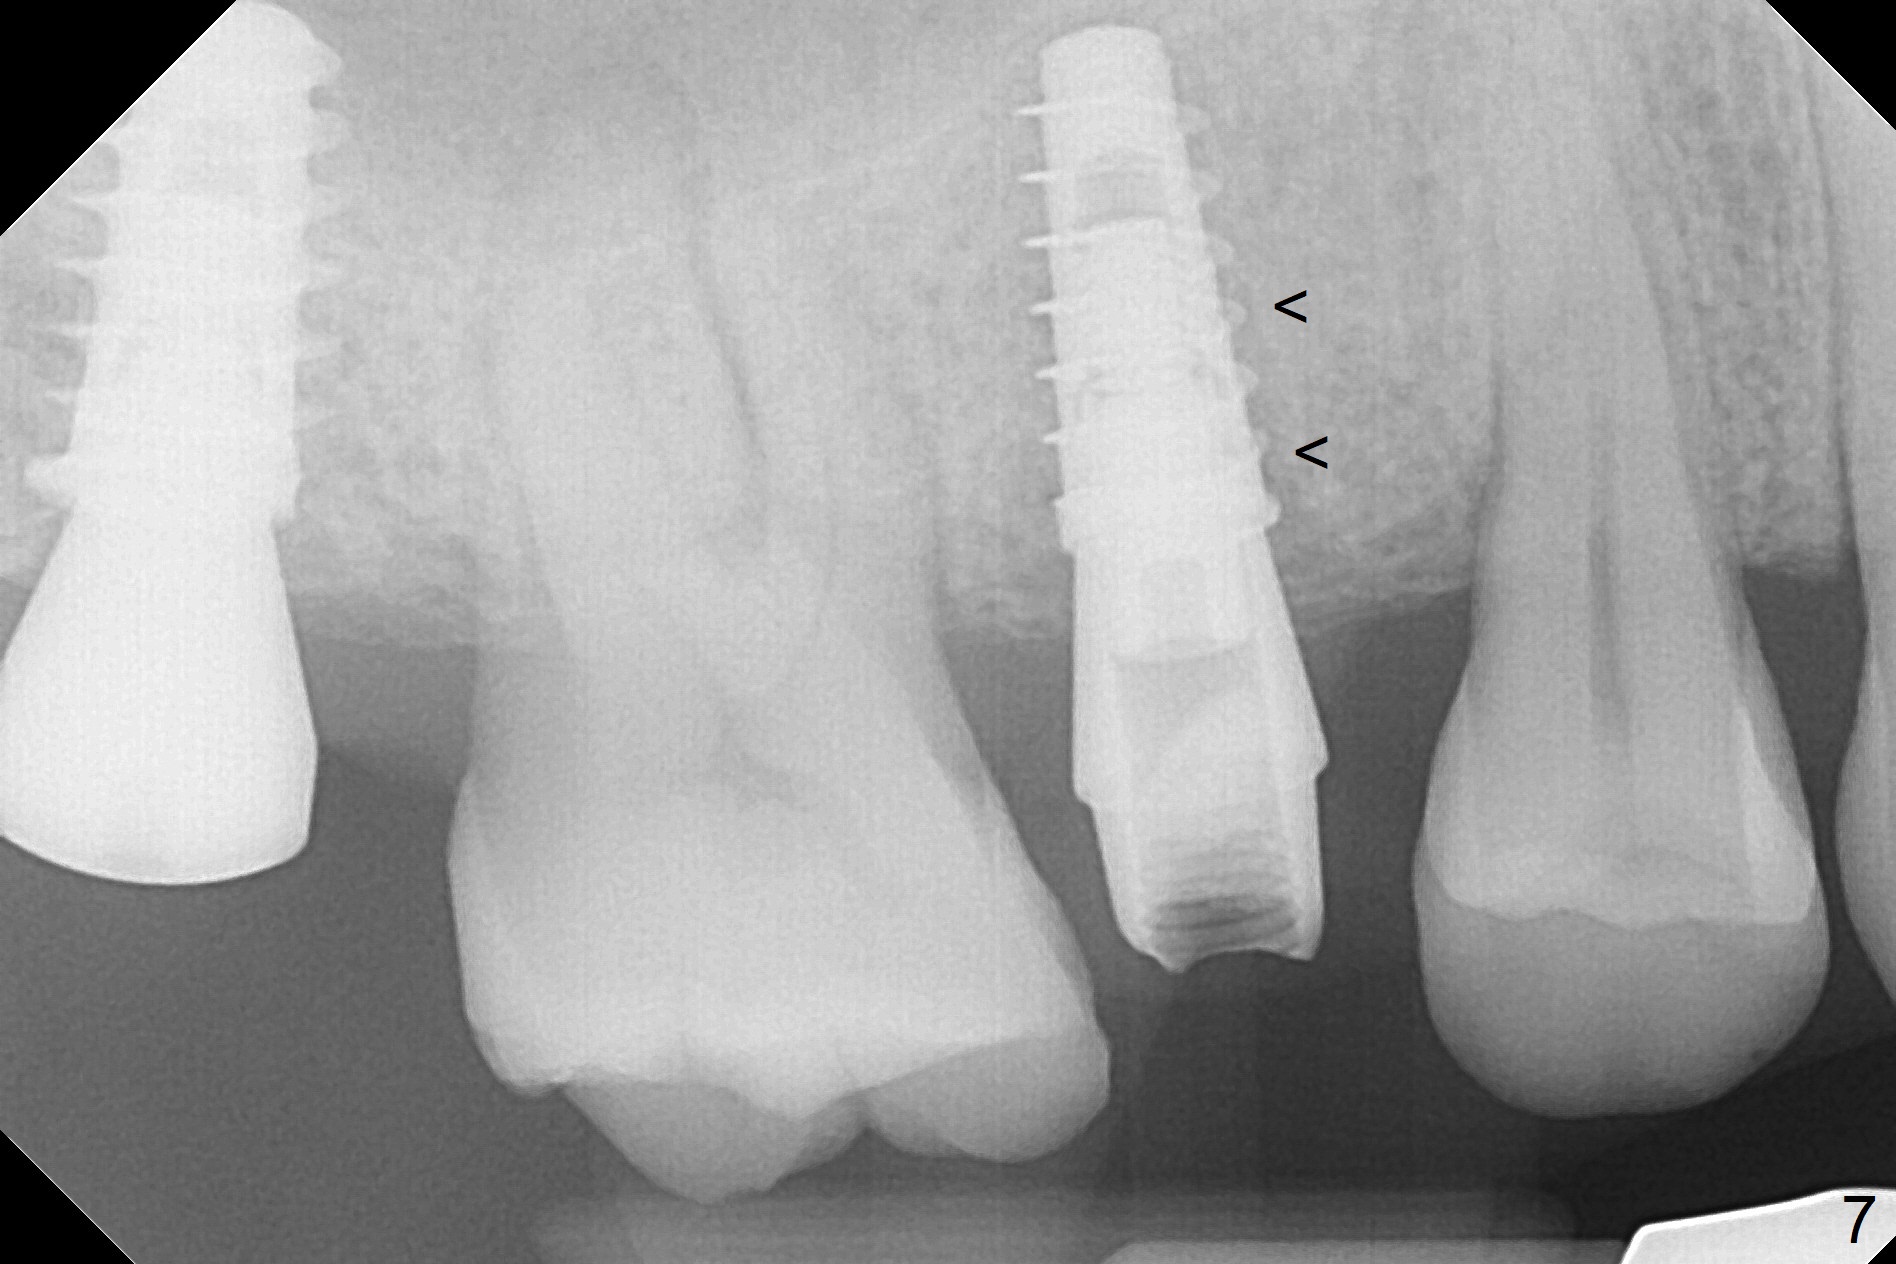

A 47-year-old man returns emergently with subgingival fracture of the lingual (L) cusp of the tooth #4 (Fig.1-3).  After extraction (no bony defect) without drilling, a 4x11 mm dummy implant is placed as a tap drill with satisfactory stability (Fig.4,5).  To get subcrestal placement, a shorter (4x9 mm) implant is inserted with insertion torque of < 35 Ncm.  In retrospect, a larger implant (4.5 mm) would be better in term of primary stability.  After allograft placement into the buccal and lingual gaps, a 4.5x4(4) mm abutment is placed for an immediate provisional.  There is a peri-implant gap 7 months postop (Fig.7<, as compared to the implant at #2 (6 months postop)) .  When the loose abutment is being retightened, the patient feels pain, although the gingiva appears healthy (Fig.8).  A larger implant should have been used; the abutment should have been removed.  The implant dislodges while the abutment is untightened 8 months postop.  The osteotomy is found intact.  A 4.5x11 mm dummy implant is placed 2 mm subgingival with 20 Ncm (Fig.9).  When a 4.5x11 mm definitive implant is placed 3 mm subgingival (Fig.10,11), torque reaches 50 Ncm.  A 5.5x3 mm healing abutment is placed.  Three months postop, the implant is stable (Fig.12,13) and impression is taken.